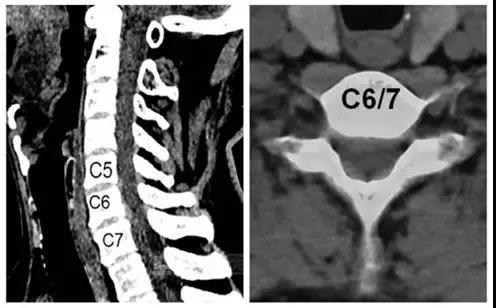

术前CT

术前核磁

诊断:颈椎病(C6/7)

患者:男,35岁

主诉:外伤后肩颈部疼痛伴左上肢放射痛、麻木10天